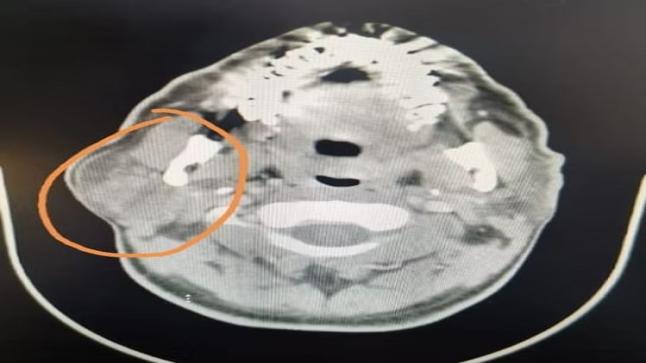

وصل مريض يبلغ من العمر 53 عامًا إلى مجمع الملك فيصل الطبي سشكو من ضعف عام للجسم وكذلك ظهةر تشنجات عصبية وعلى الفور تم الكشف عليه وعمل الأشعة والتحاليل اللازمة وتبني أنه يعاني من وجود ورم في الدماغ موجود في الناحية اليمنى في المخ.

وفي وقت قصير جدا تم تجهيز المريض من أجل التدخل الجراحي تحت مخدر عام وبعد ذلك تم فتح الجمجمة واستئصال الورم من الدماخ في الفص الأمامي من الناحية اليمنى والفص الجبهي من المخ.